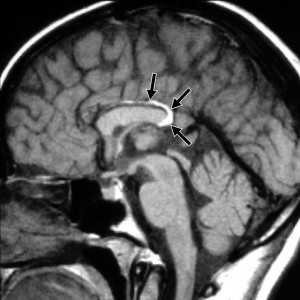

МРТ имеет большие диагностические возможности. В типичных случаях в зоне локализации опухоли выявляют в Т1W низкоинтенсивный сигнал, а в Т2W-высокоинтенсивный сигнал, не изменяющийся после контрастирования гадолинием. Сигнал не всегда отличим от ликвора, что затрудняет постановку диагноза ЭО. Так, Shinoda и соавторы в 1995 г. описывали случай, когда у больного с тригеминальной невралгией была интраоперационно обнаружена ЭО мостомозжечкового угла, недиагностированная при МРТ [37]. В связи с этим, выделяют дополнительные признаки ЭО при МРТ: 1) минимальный масс-эффект при больших размерах опухоли; 2) неровный "зубчатый" контур очага; 3) отсутствие перитуморального отека; 4) гидроцефалия обычно не выражена и не соизмеряется с размерами опухоли; 5) сигнал не изменяется после контрастирования [45].

Проявления на МРТ схожи с таковыми на КТ; эпидермоиды часто неотличимы от арахноидальных кист или расширенных ликворных пространств на многих последовательностях.

- T1

- обычно изоинтенсивны ликвору

- часто наблюдается более интенсивный сигнал по сравнению с ликвором по периферии образования

- обычно неоднородный / "грязный" сигнал; выше, чем от ликвора

- остерегайтесь потоковых артефактов от пульсации ликвора, которые могут имитировать подобные изменения